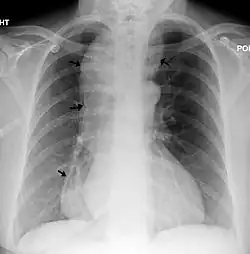

A chest X-ray showing achalasia (arrows point to the outline of the massively dilated esophagus)